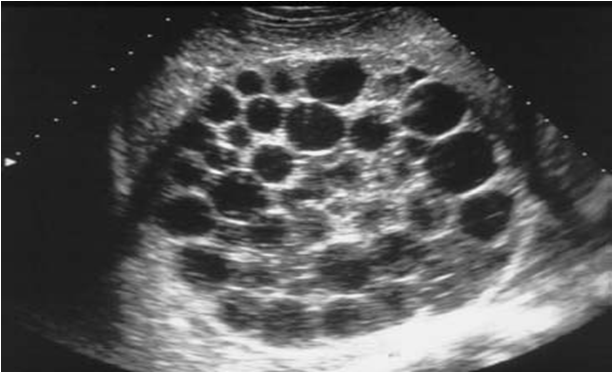

30 year old male presents for a renal ultrasound

liver & spleen cysts

Adult Polycystic Kidney Disease